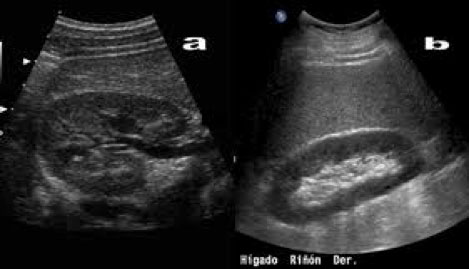

¿Cómo se ve un riñón con ecografía?

El riñón suele tener un contorno liso, a veces es lobulado, tiene un tamaño aproximado de 10,5 – 11 cm.

En un riñón normal se distinguen dos zonas importantes la cortical que es hipoecogénica y el seno renal que es hiperecogénico.

Es importante la valoración del hilio, con la arteria, vena renal y la unión ureteropiélica que se continua con la porción proximal del uréter, el resto del uréter suele ser más difícil de visualizar excepto cuando este dilatado.